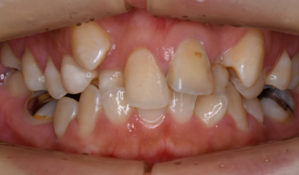

マウスピース型矯正装置(インビザライン)の症例

マウスピース型矯正装置(インビザライン)を使用した歯列矯正

八重歯/ガチャ歯

ガタガタ(叢生)